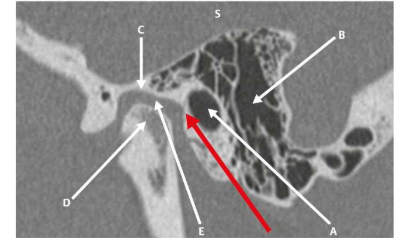

A orelha externa é a parte visível sendo composta pelo pavilhão auricular e pelo conduto auditivo externo, (CAE). O pavilhão auricular é composto por cartilagem, recoberto por pele e é responsável pela captação do som e seu direcionamento para o canal auditivo externo. Ilustração em janelamento ósseo auricular.

Fonte: Pauna, Henrique, F. et al. Avaliação do Osso Temporal por Imagem: Uma Abordagem Radiológica e Histológica., Thieme Brazil, 2024.

De acordo com a ilustração, assinale a alternativa incorreta.